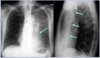

What are the arrows pointing to in this CXR?

* Anterior Mediastinal Mass * Need lateral CXR to confirm. It's hard to see the mass in AP view.

90